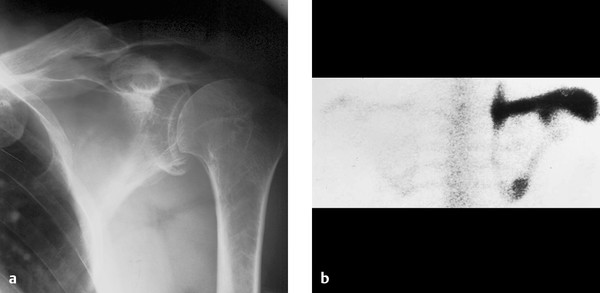

The spine of the scapula is almost a bone of its own. Christi galli cribriform plate orbital roof nasal conchae. Spine of the scapula reformatted ct image. For a random human anatomy question every day on your phone you can get my daily anatomy question app from.